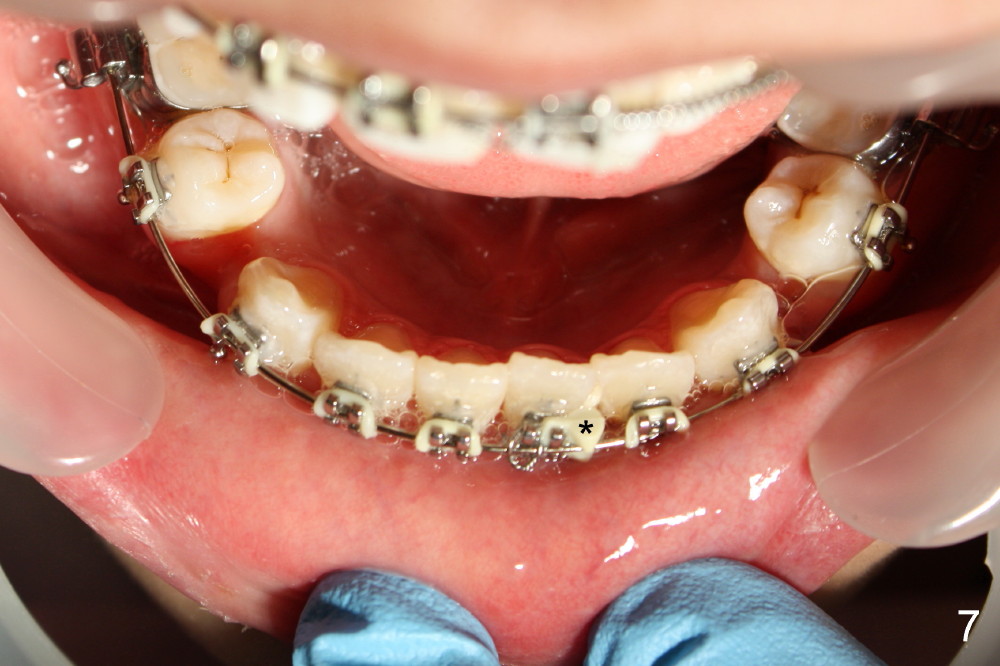

Correction of crowding for the lower anterior region is much easier. A rotation wedge is placed about 1 month post bracketing (Fig.4 (photo taken 2 months post bracketing)). Progress of correction is shown in Fig.7,8 (4,5 months post bracketing).